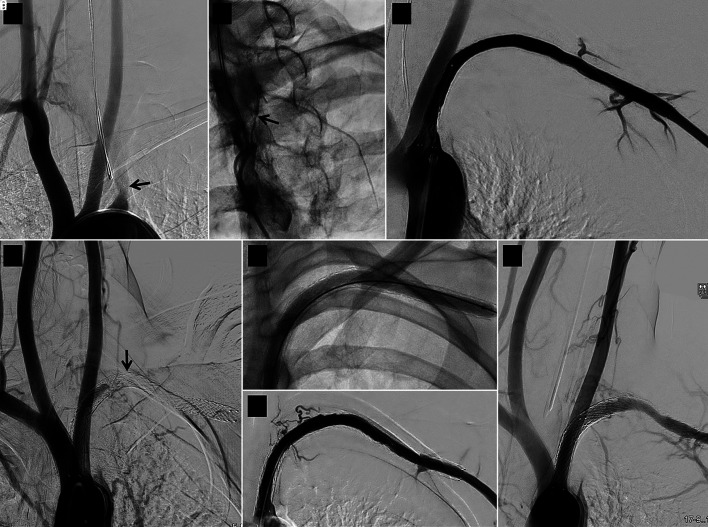

Figure 1.

Serial angiographic images of a case relating to stent 16 in the study. (a) Baseline image showing long left subclavian artery occlusion starting in the proximal segment (arrow). (b) A narrow track (arrow) is seen leading into the occlusion on wedge angiography. (c) Good immediate result after recanalization, 5 mm diameter balloon dilatation and implantation of a 7 × 120 mm self-expanding stent. (d) Follow-up angiogram 6 months later showing stent occlusion (arrow); this was treated by a second intervention that included 6 mm diameter balloon dilatation (e) achieving a good result immediately (f) and 11 months after the second intervention (g).